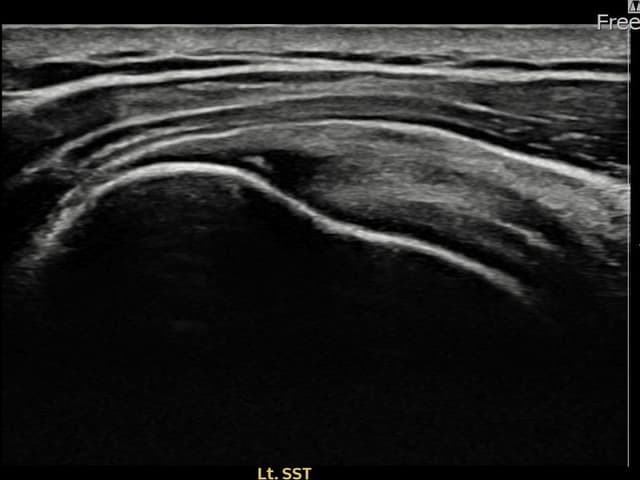

[촬영시기:24.01.08~24.03.14]

[어깨인대 축소봉합술] 좌측 어깨 통증으로 팔을 올리기 불편하여 내원하셨습니다.